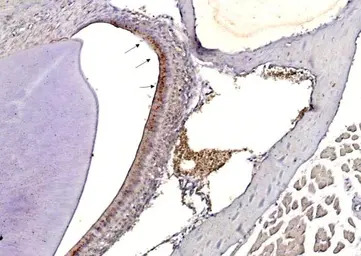

Influenza A Virus H3N2 Hemagglutinin (HA) antibody detects Influenza A Virus H3N2 Hemagglutinin (HA) protein on mouse nasal tissue(infect with Influenza Virus A ) by immunohistochemical analysis.

Sample: Paraffin-embedded mouse nasal tissue(infect with Influenza Virus A ).

Influenza A Virus H3N2 Hemagglutinin (HA) antibody (GTX127363) dilution: 1:50.

Antigen Retrieval: Trilogy™ (EDTA based, pH 8.0) buffer, 15min